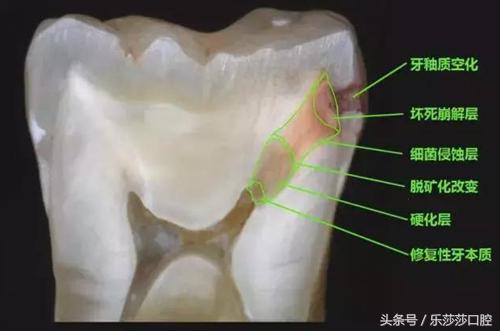

十七、蛀牙蛀洞下的结构改变。